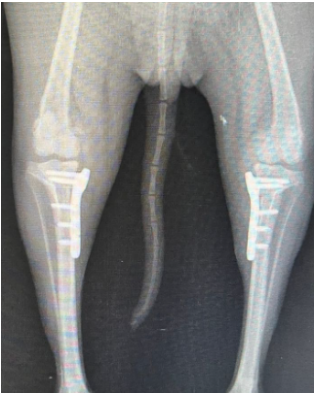

今天与大家分享来自巴西Dr. Fred Ribeiro TPLO双侧手术案例。

品种:德国斯宾兹犬

性别:雄性

年龄:5岁

体重:5Kg

2.0mmTPLO锁定骨板,左和右;

螺钉长度8、10、12和16mm。

术后X光